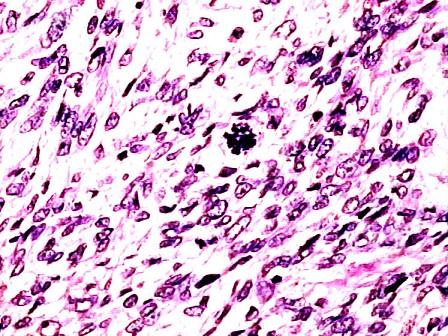

问题 图为纤维肉瘤之镜下观,有关其异型性错误的描述是 ( )

选项 A.肿瘤细胞呈束状排列 B.肿瘤细胞丰富,排列紧密 C.肿瘤细胞体积大,并且大小不一 D.可见病理性核分裂像 E.肿瘤细胞核与胞浆比例正常

答案 E